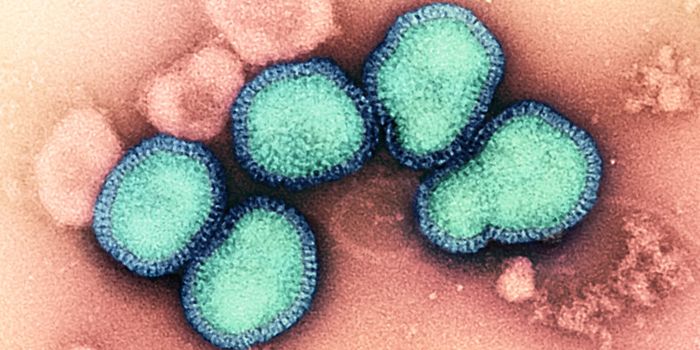

JUL 29, 2024MicrobiologyThe H5N1 avian influenza is highly pathogenic and has been devastating bird populations worldwide. It continues to ...

JUL 28, 2024MicrobiologyHighly pathogenic avian influenza could once only be caught from an infected bird. But it seems the virus can now move f ...